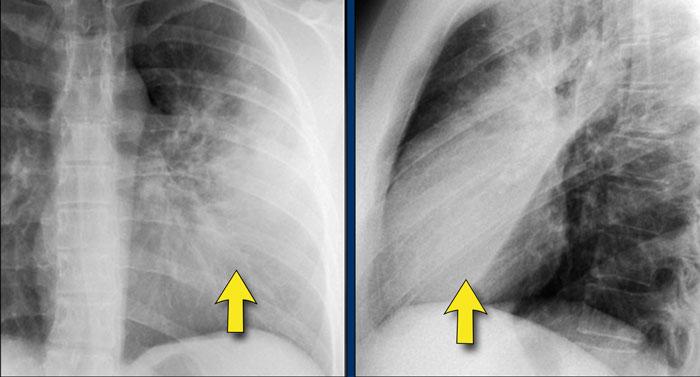

1. Không có dấu hiệu silhouette trong đám đông đặc ở thùy dưới trái (mũi tên xanh dương). 2. Dấu hiệu silhouette trong đám đông đặc ở thùy lưỡi (mũi tên vàng).

Dấu hiệu Silhouette

Dấu hiệu silhouette đề cập đến sự mất đường bờ bình thường giữa các cấu trúc có tỷ trọng X-quang khác nhau, thường gặp nhất là phổi chứa khí tiếp giáp với các cấu trúc phần mềm như tim hoặc cơ hoành.

Dấu hiệu này có vai trò quan trọng trong việc phát hiện các tổn thương kín đáo và định khu tổn thương trong lồng ngực.

Minh họa Dấu hiệu Silhouette

- Không có Dấu hiệu Silhouette (Mũi tên Xanh dương)

- Tâm thất trái, nằm ở phía trước, bình thường được tiếp giáp với thùy lưỡi chứa khí của thùy trên trái.

- Nếu đông đặc xảy ra ở thùy dưới trái (phía sau), ranh giới giữa thùy lưỡi và tim vẫn còn nguyên vẹn, và bờ tim trái được bảo tồn.

- Dấu hiệu Silhouette Dương tính (Mũi tên Vàng)

- Khi đông đặc hiện diện ở thùy lưỡi, vùng này tiếp giáp trực tiếp với bờ tim trái, làm mờ bóng của tâm thất trái.

- Điều này cho thấy tổn thương nằm ở phía trước lồng ngực.

Ca lâm sàng 2: Tư thế PA

- Quan sát thấy đám đông đặc ở thùy dưới trái (mũi tên vàng).

- Bờ tim trái vẫn được xác định rõ với bóng silhouette bình thường (mũi tên xanh dương), cho thấy tổn thương nằm ở phía sau và không liên quan đến thùy lưỡi.